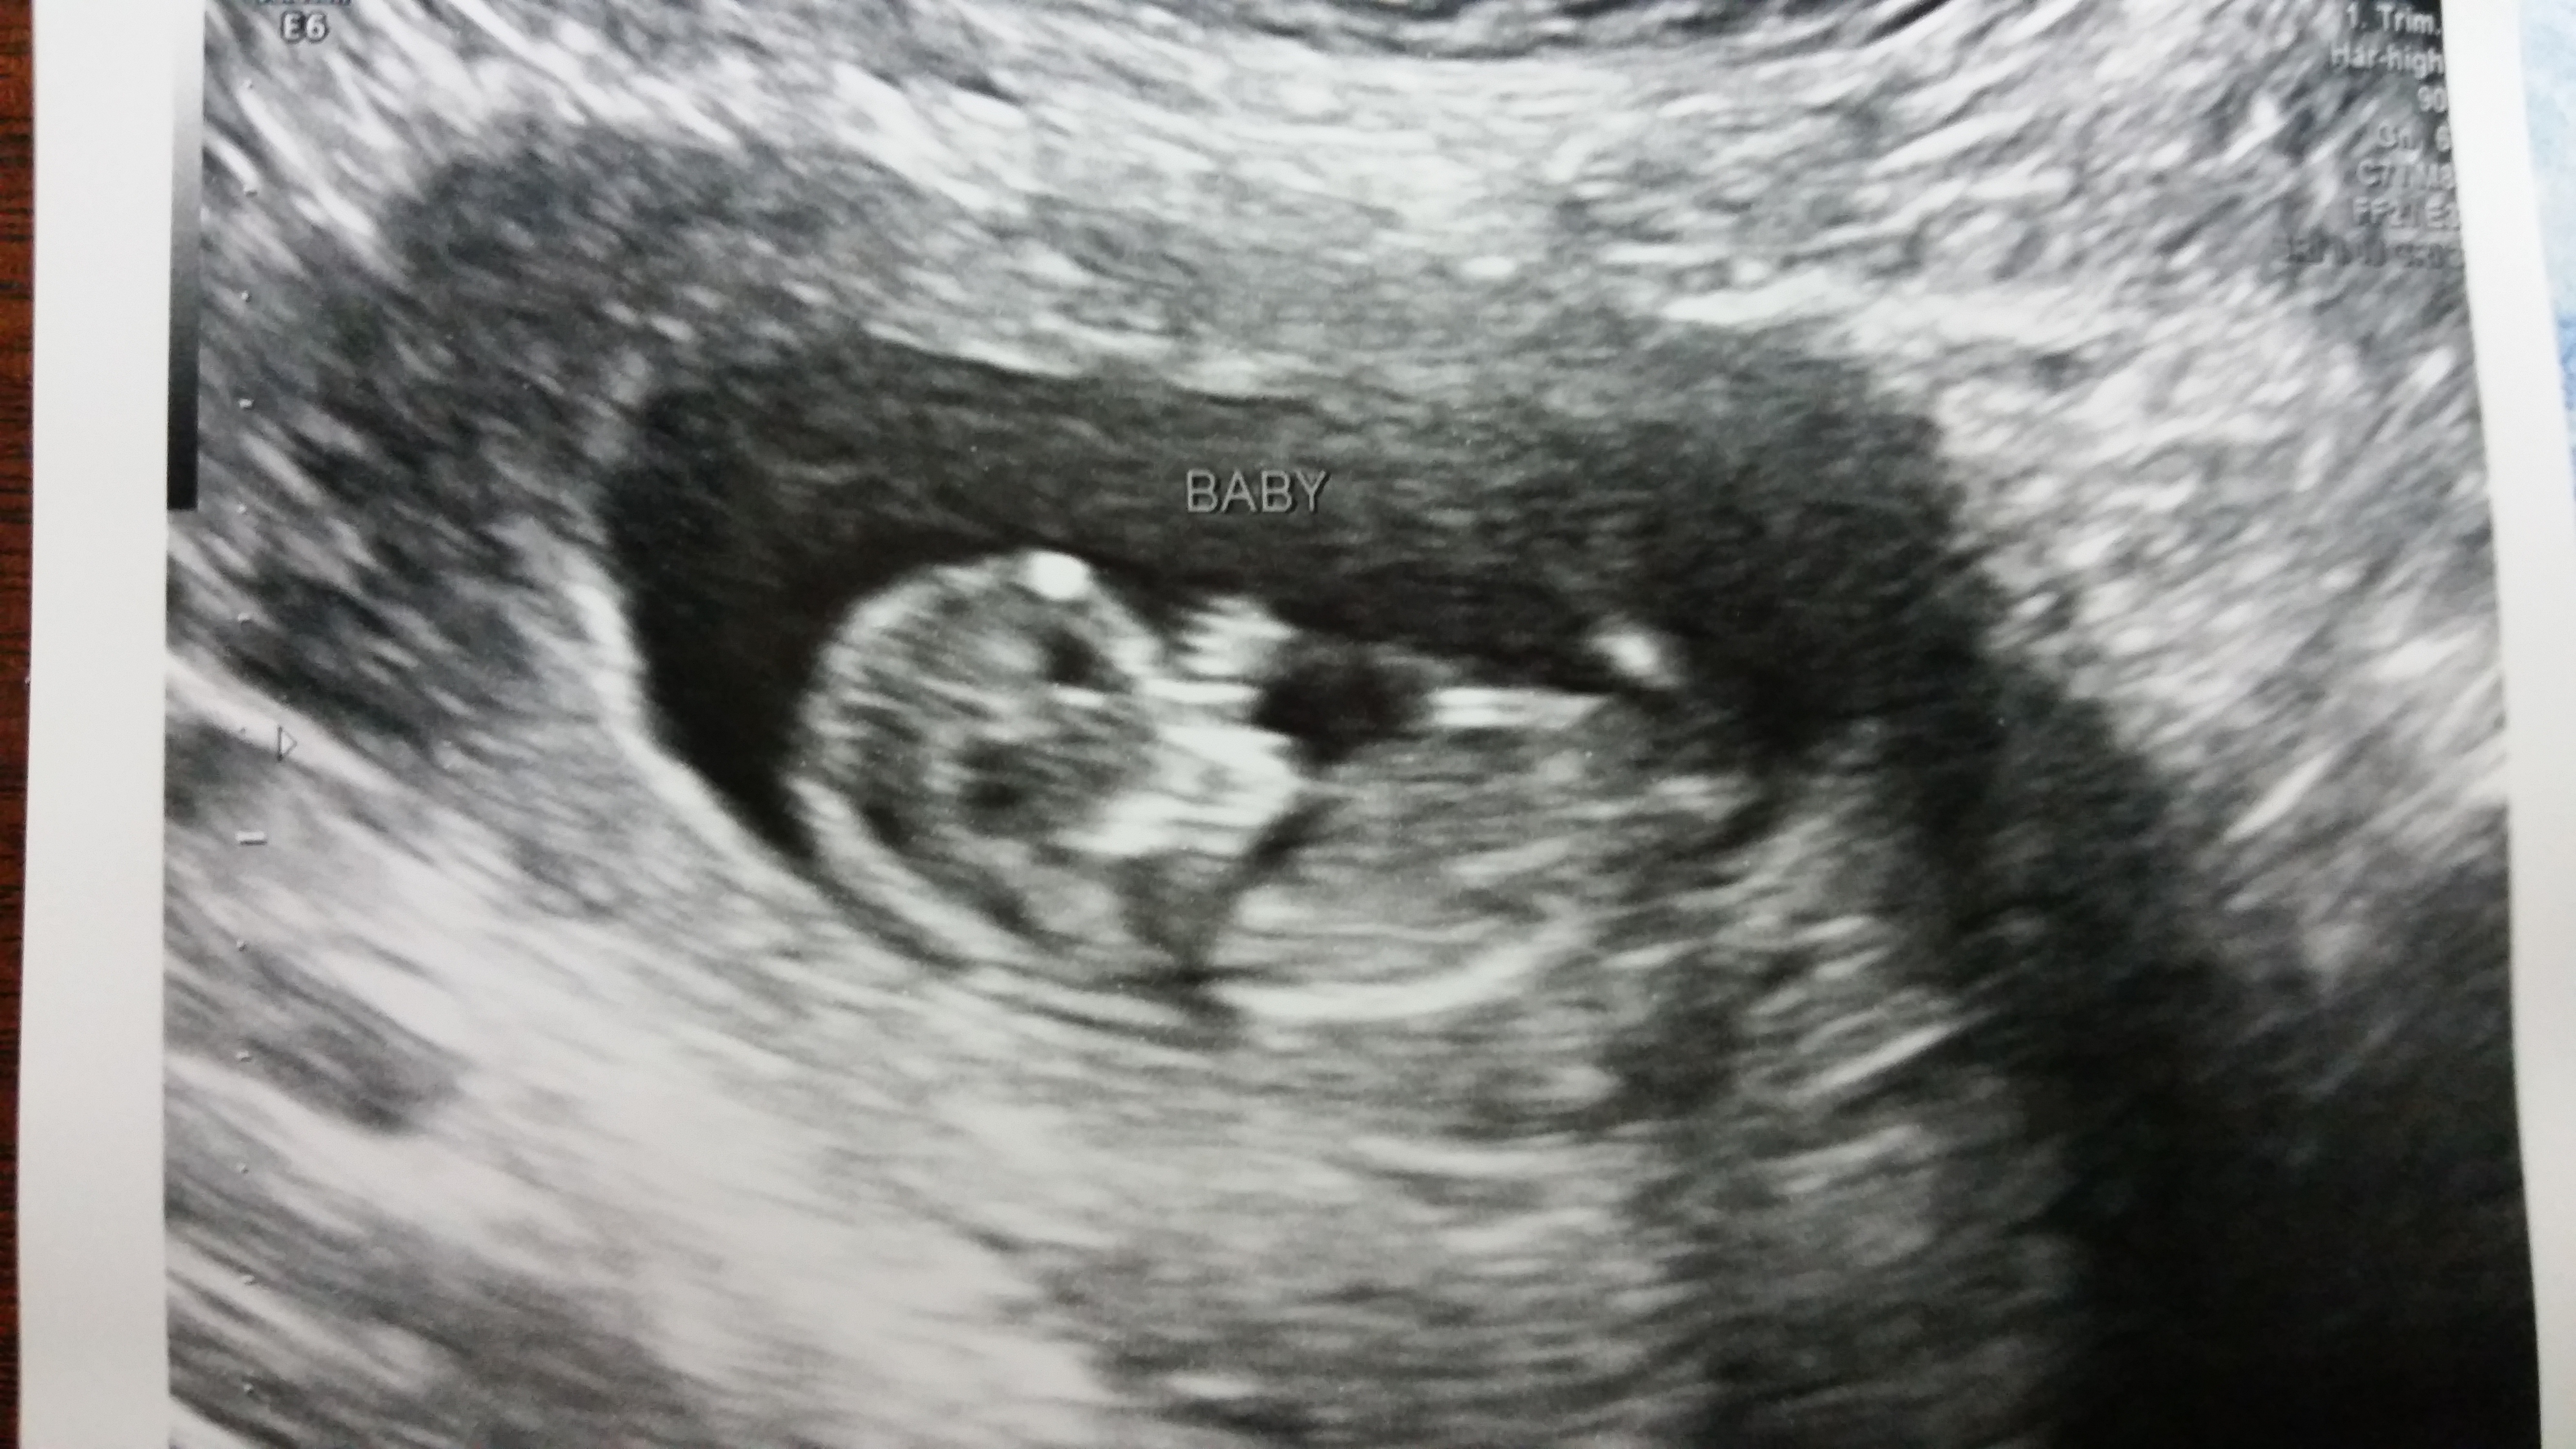

Hey all! So my US went great today. The measurements all came back perfect. I did get my 1st tri screen as well and they are going to do a baseline 24hr urine just to see. All in all, great visit (even if the MFM specialist is one of my students' mom!)

@kbrands7 I missed why you had to have the ultrasound but so relieved for you things are good. But now, can we talk about those baby fingers?!?! Aghhh can't wait for my next scan, so precious!!

I love the fingers too! It was so amazing to see little one bopping around and putting fingers in his/her mouth. :x I hope you get to see some cuteness (and of course a healthy baby) during your next scan!